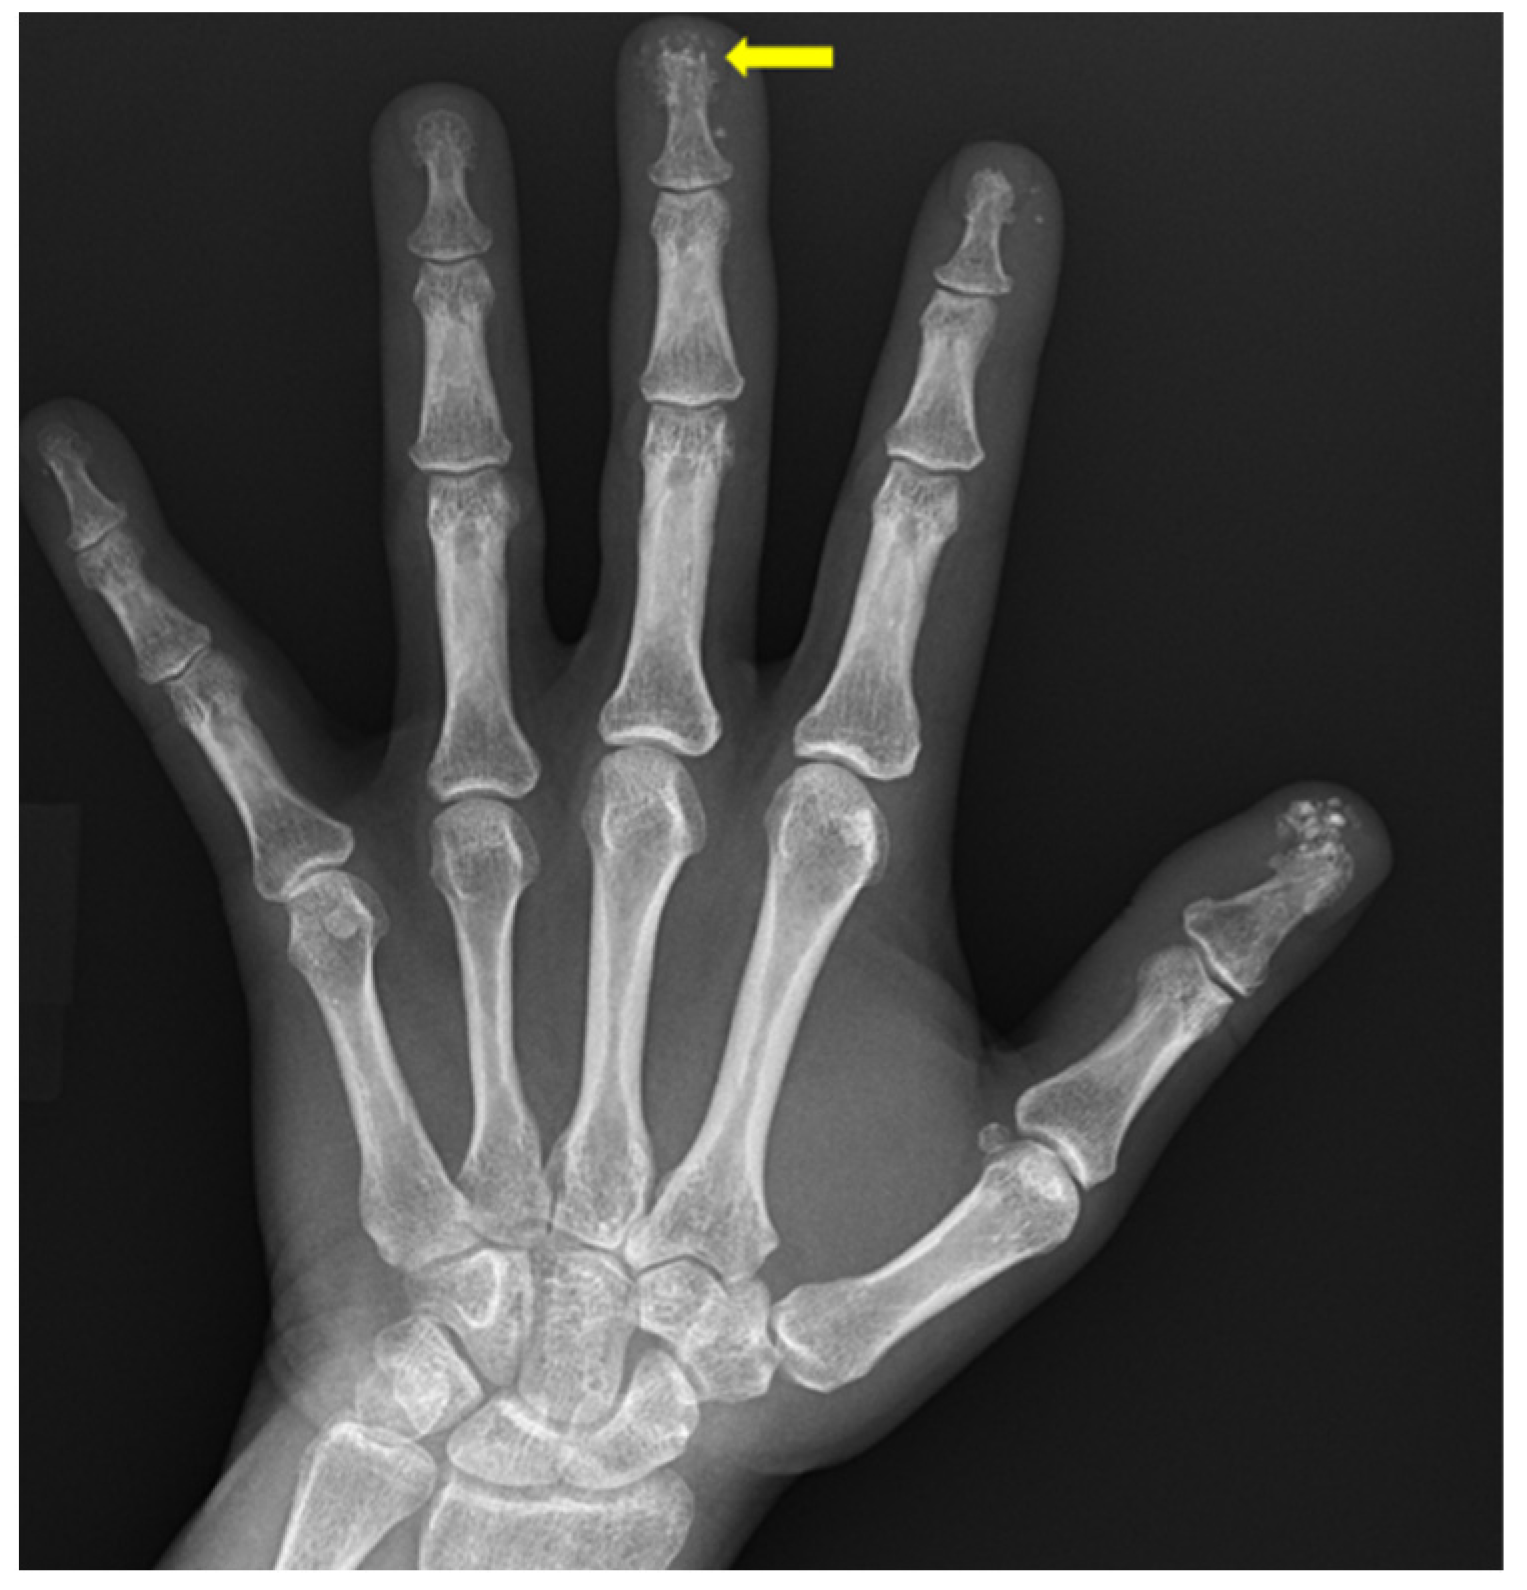

4. Rheumatoid Arthritis